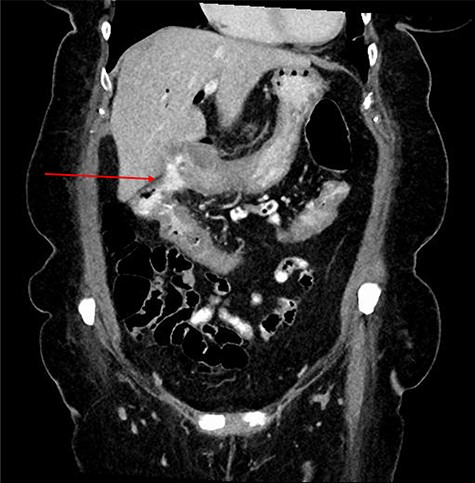

Computed tomography (CT) revealed a complex fistulous communication between the distal stomach and biliary tree with associated pneumobilia, and between the transverse colon and the distal stomach (Fig. 1). No gallstones were seen. Upper and lower gastrointestinal endoscopy was performed, revealing a prepyloric gastric ulceration and fistula (Fig. 2), with no obvious gastric pathology, which extended into the colon and a blind end structure assumed to be the gallbladder. Colonoscopy demonstrated an area of slight narrowing from the hepatic flexure to mid-transverse colon, with macroscopic colitis (Fig. 3). Biopsies were non-specific, with IBD a possibility, but the features were not pathognomonic.

CT abdomen and pelvis demonstrating fistulous communication between distal stomach and transverse colon (red arrow) with pneumobilia.